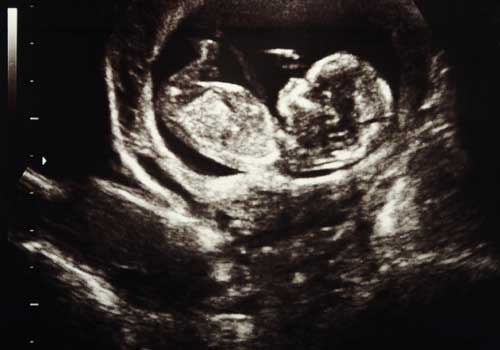

Το κέντρο προγεννητικής Διάγνωσης ιδρύθηκε το 2006 στην Πάτρα και προσφέρει εξειδικευμένη φροντίδα στις εγκύους από την Ιατρό Μαιευτήρα-Γυναικολόγο Νικολοπούλου Νταίζη (Διονυσία), ειδικευθείσα στον προγεννητικό έλεγχο στο κέντρο Harris Birthright Recsearch Centre for Fetal Medicine Λονδίνο, υπό την αιγίδα του Fetal Medicine Foundation, London.

Σκοπός μας είναι η προσφορά υψίστης ποιότητας υπηρεσιών προγεννητικού ελέγχου και συμβουλευτικής στους νέους γονείς.